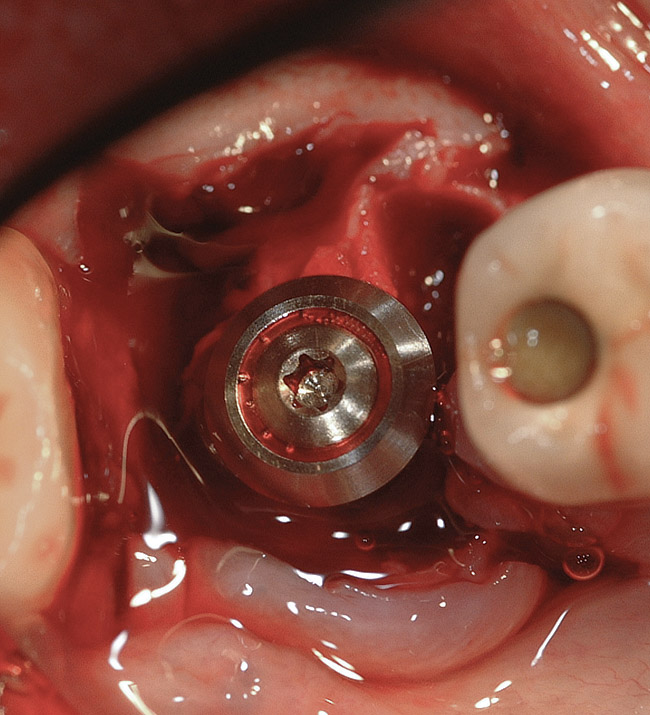

Figure 14  An implant with a 4.8-mm-wide body and a 6.5-mm-wide restorative platform was placed in the interradicular bone following appropriate preparation.

Figure 14

Figure 15  Another view of the implant in the interradicular bone. Note that the mesial and distal aspects of the interradicular septum have been lost. The implant attained primary stability from the buccal and lingual aspects of the interradicular bone.

Figure 15